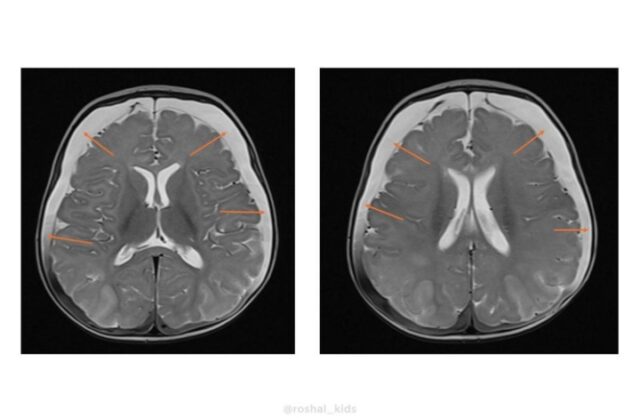

Как узнал «МК», в медучреждение в тяжелом состоянии привезли четырехмесячную девочку. У ребенка случился судорожный приступ. Обследование выявило пугающие симптомы: выпирающий родничок, увеличенный размер головы и критически высокий, почти в пять раз выше нормы, уровень аммиака в крови (194 мкмоль/л при норме до 47). Врачи выяснили, что у маленькой пациентки оказалось крайне редкое генетическое заболевание: ННН-синдром. Это нарушение цикла мочевины, врожденный сбой в обмене веществ. Организм не может перерабатывать белок, из-за этого происходит отравление аммиаком, буквально разрушающее мозг.